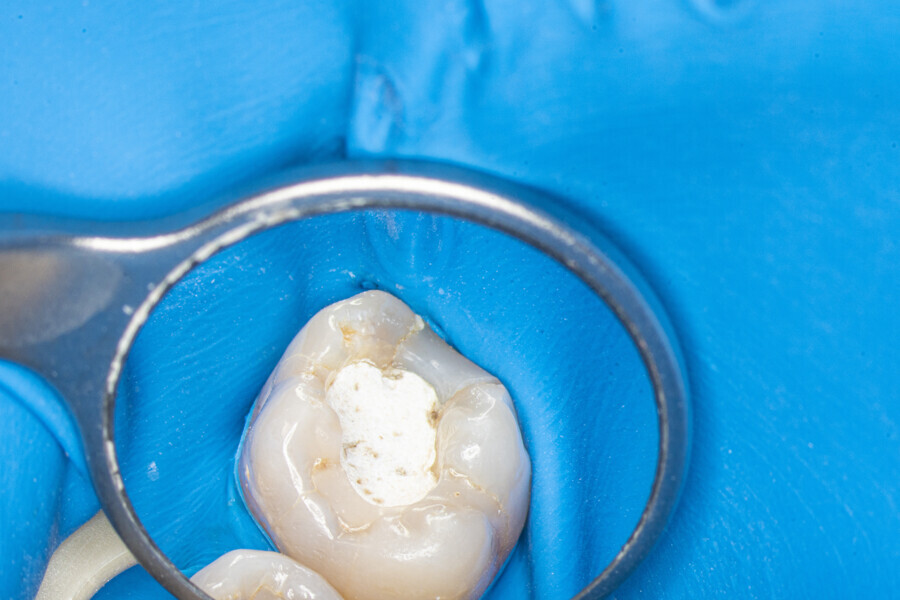

The first trials of the LPE concept were performed on extracted human molars. Although the dynamics of fluid during root canal irrigation are completely different in vivo than in extracted teeth, these kinds of trials provide initial information about the procedure. Some of these teeth had apices closed with a coat of wax and composite resin to close the apical delta and simulate the periapical tissue. After creation of the access cavity, the pulp chamber was cleaned with continuous irrigation with 5.25% NaClO activated with a SkyPulse laser (Fotona) in AutoSWEEPS mode (20 Hz, 15 mJ). A 25/0.07 reciprocating file (Shenzhen Perfect Medical Instruments) was used to perform the pre-flaring procedure. After opening the coronal third, continuous irrigation with 5.25% NaClO activated with the laser was used to clear the debris for 30 seconds. After removing the debris, a #10 C-PILOT file (VDW) was used to establish apical patency, without forcing the file if possible. In some cases, apical patency was reached already at this stage of root canal preparation. In all cases, the second step of instrumentation was the preparation of the middle third with the same file, and the same irrigation procedure was performed. Subsequently, the C-PILOT file was used to reach the apical foramen. At this stage, apical patency was reached in most cases, but in some roots, there was no possibility of entering the apical foramen. The working length was confirmed with a radiograph with the hand file. Usually, the next procedure to be done is apical preparation, but the LPE concept is based on an enhanced irrigation protocol. Following this protocol, irrigation was performed for 5 minutes with continuous flow of 5.25% NaClO activated with the SkyPulse laser in AutoSWEEPS mode (20 Hz, 20 mJ) with a conical sapphire fibre. The next step was alternating irrigation with 17% EDTA for 30 seconds, with 5.25% NaClO for 30 seconds and with 17% EDTA for 30 seconds, all activated with AutoSWEEPS, followed by irrigation for another 5 minutes with 5.25% NaClO activated with AutoSWEEPS. In most cases, the next step after this stage of enhanced irrigation was the calibration of the apical constriction rather than apical preparation per se, but this step requires further investigation.

Case 1 (Figs. 7–26)

Case 2 (Figs. 27–36)

Case 3 (Figs. 37–46)

Case 4 (Figs. 47–60)